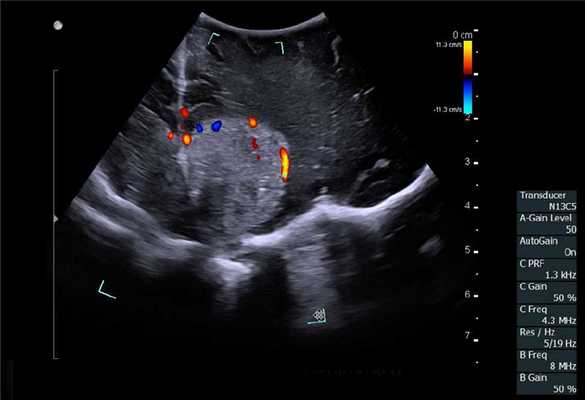

В случае выявления образований в печени и измененных забрюшинных лимфатических узлов (при необходимости) выполняли пункционно-аспирационную биопсию. При этом образование, эхографически подозрительное на метастатический узел, располагалось по центру сканирующей поверхности датчика и тем самым по центру монитора. При исследовании обязательно использовали методику допплерографии для выбора участков с наименьшим кровоснабжением. Эта же методика позволяла визуализировать кровеносные сосуды над узловым образованием и избежать их повреждения. После выполнения указанных моментов выполняли непосредственно пункцию.

Гемангиома серпа головного мозга. Сканирование нейрохирургическим датчиком 8862

Отечественные и зарубежные авторы доказали высокий уровень корреляции между данными, полученными при интраоперационном УЗИ и послеоперационной МРТ с контрастным усилением при обнаружении остаточной опухолевой ткани [16,17]. При этом применение режимов допплерографии, а также контрастного усиления значимо повышают информативность исследования. Цветовое допплеровское картирование при сосудистых аномалия позволяет не только локализовать аневризму, но и вместе со спектральной допплерографией провести оценку гемодинамических показателей, например, после клипирования аневризмы.